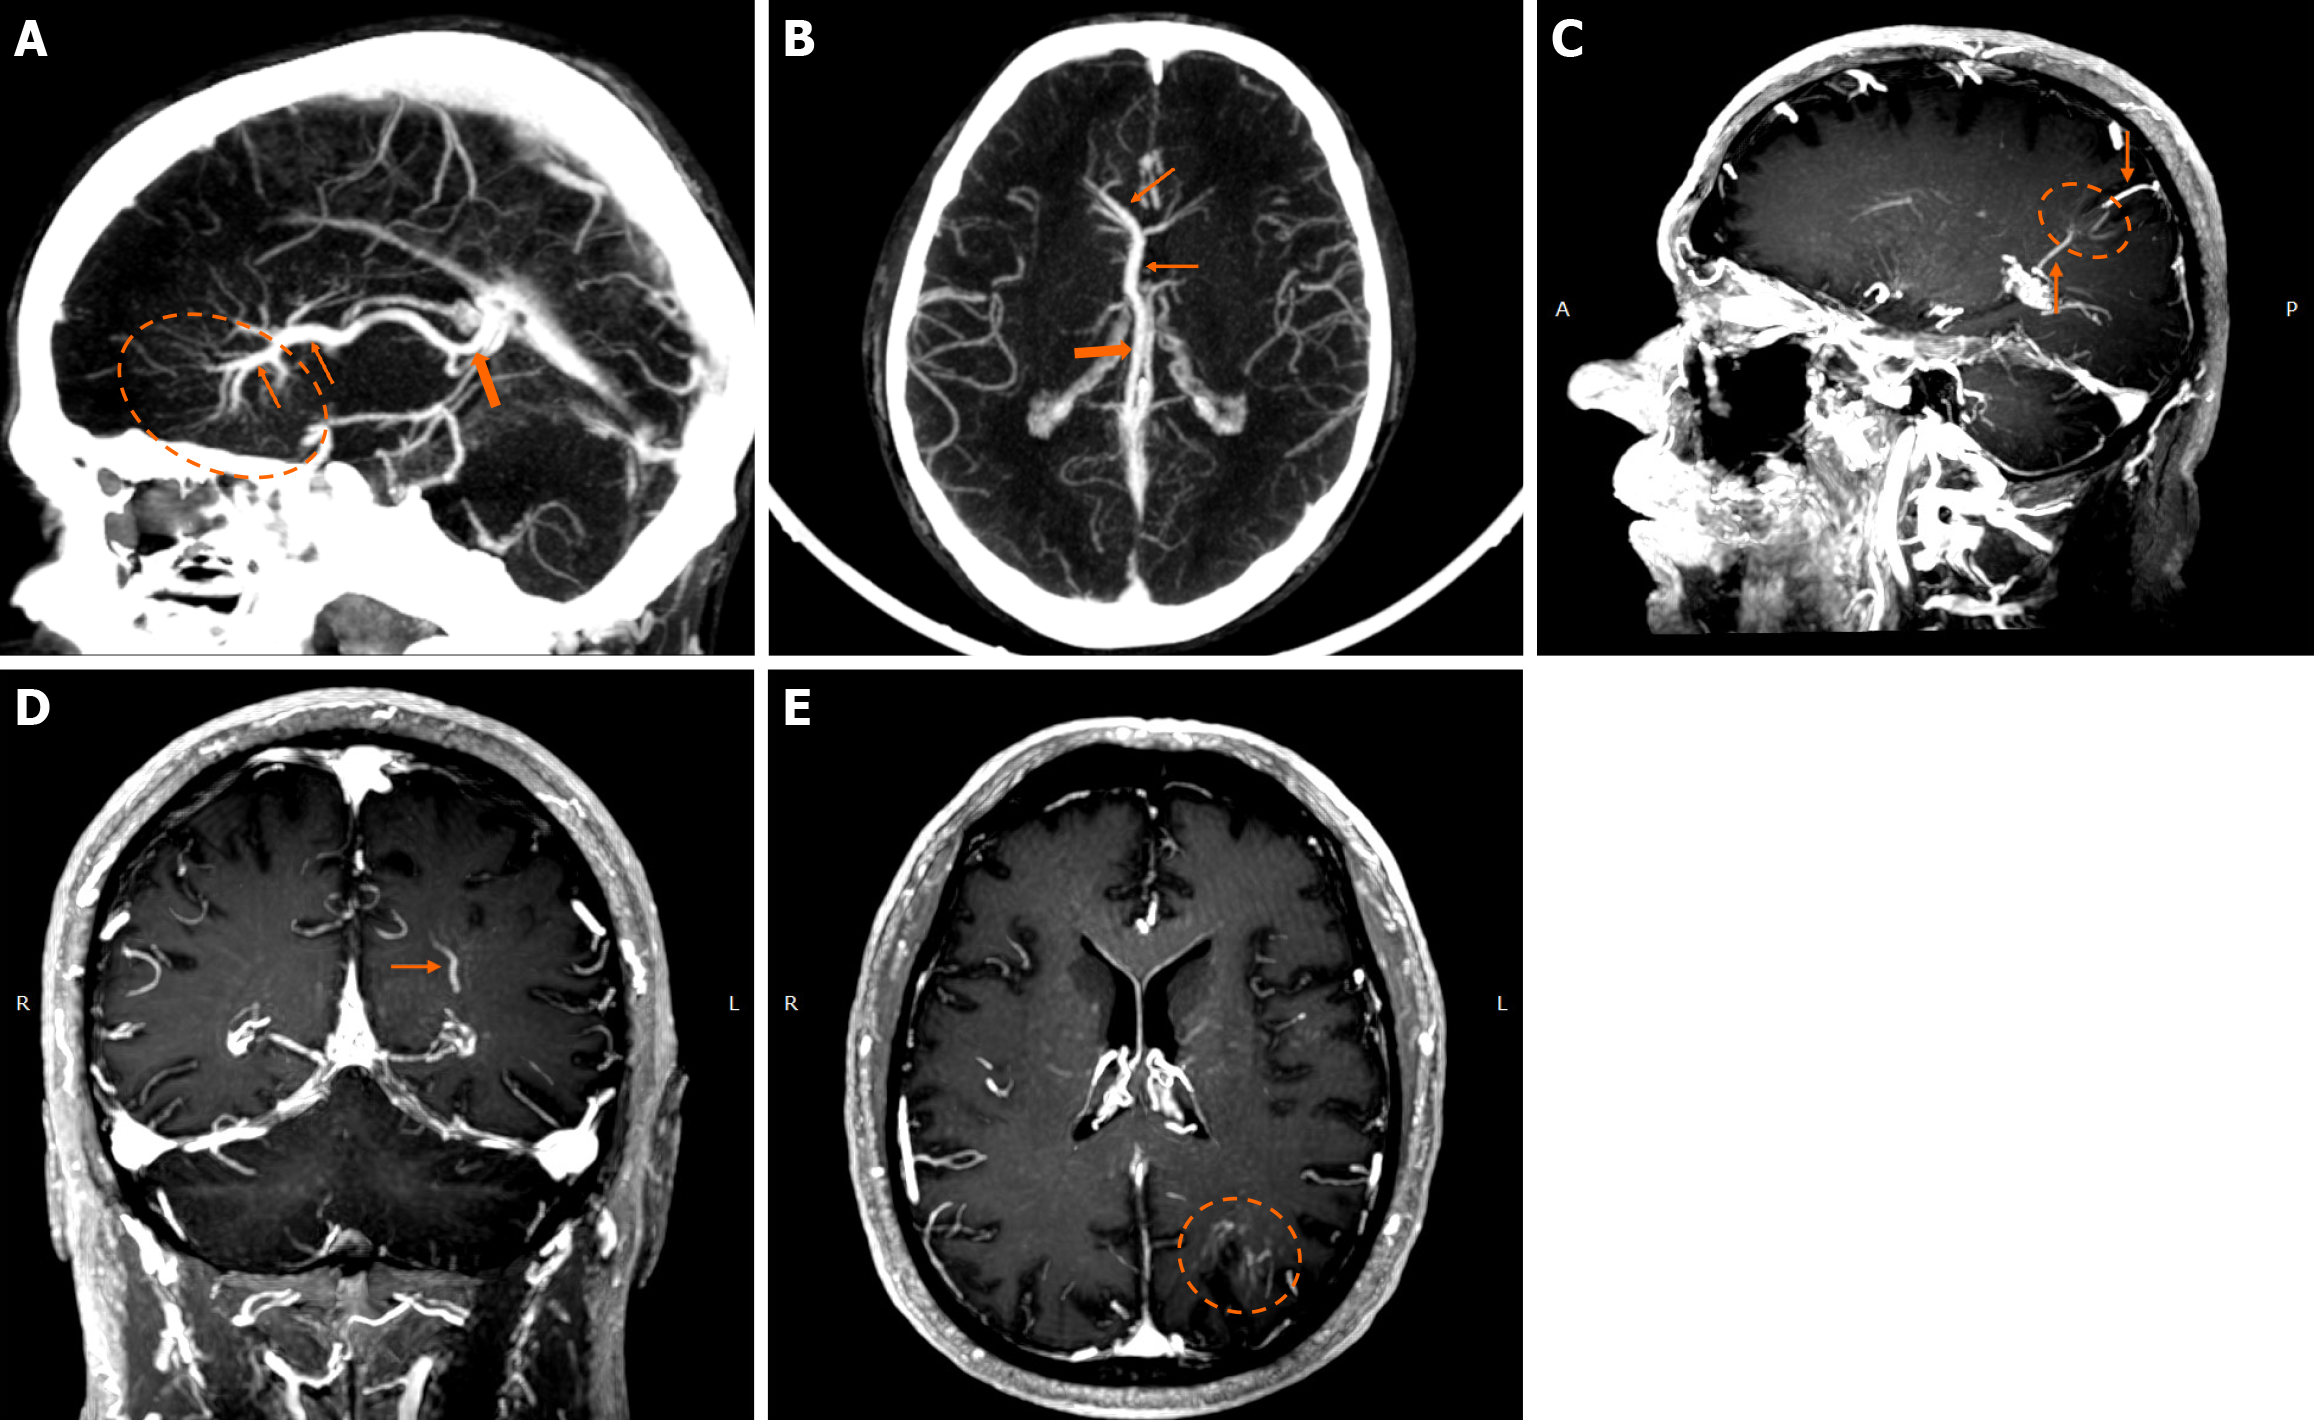

On non-contrast CT, smaller DVAs may not be visualized, while larger ones with a patent collecting vein may appear isodense or slightly hyperdense compared to the brain cortex. A thrombosed collecting vein may appear markedly hyperdense[45]. Non-contrast scans can also assess locoregional parenchymal abnormalities (i.e., calcifications) in the drainage territory[48]. Post-contrast brain CT, typically performed 2-3 minutes after contrast administration, provides clearer visualization of the characteristic “caput medusae” morphology and the collecting vein, both of which enhance[10]. A “caput medusae” morphology is defined as multiple radially oriented veins that converge centrally to the collecting channel[49]. Dedicated CT angiography, usually with bolus tracking, and/or venography with 50 second-delay can provide more information on the morphology of the DVA but are usually not necessary[3,5]. Some DVAs may show ampullary dilatation of their proximal portion at the convergence of the medullary veins[10]. Newer CT technologies with dynamic subtracted angiography provide more detailed morphological visualization[5].

DVAs are often detectable across various MRI sequences but are most clearly visualized on post-contrast T1-weighted (T1w) and susceptibility-weighted imaging (SWI) sequences[7]. Smaller DVAs can be overlooked, even in post-contrast series. In a study by Gökçe et al[7], almost half of the DVAs were not visible on non-contrast sequences. The collecting vein is more easily visualized than the “caput”[12]. DVAs typically appear as flow voids on both T1w and T2w sequences and may demonstrate phase-shift artifact[3]. The radicles may sometimes have a high signal at fluid-attenuated inversion recovery (FLAIR) images, which should not be confused with parenchymal changes[51]. They show homogeneous enhancement after gadolinium contrast administration. Their visualization is enhanced by three-dimensional (3D) gradient-echo (GE) T1w sequences, which provide high-resolution imaging and allow for multiplanar reconstructions[45]. Application of 3D sequences can also allow better morphological assessment, such as stenosis of the collecting vein[5]. MR venography and time-of-flight angiography are usually not necessary, and their role is to evaluate whether there are signs of arterial components[4]. Nonetheless, non-arterialized but large DVAs may also be visualized at time-of-flight images.

Functional MRI (fMRI) depends on blood oxygen level-dependent contrast, and changes are attributed to both extravascular tissue and local capillaries and veins. Theoretically, DVAs can contribute to the fMRI signal and can potentially lead to pseudoactivations during presurgical mapping[58]. Various examples of DVAs on CTs and MRIs are shown in Figures 1 and 2.